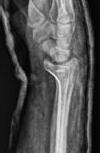

Schatzker III, Osteosinteză cu șuruburi percutană

Schatzker VI, Reducere sângerândă și osteosinteză cu 2 plăci

În fracturile Schatzker I, fără leziuni de menisc extern asociate este indicată reducerea și osteosinteza percutană cu șuruburi. Dacă leziunea de menisc este evidențiată pe RMN, se poate opta pentru reducere și osteosinteză percutană cu șuruburi asociată cu artroscopie(12), având rol de control al reducerii și curativ pentru leziunea de menisc, sau reducere deschisă și fixare internă cu placă și șuruburi.

La pacienții tineri cu fracturi Schatzker tip II și III se poate opta pentru reducere și osteosinteză percutană cu șuruburi asociată cu artroscopie. O altă variantă este cu grefă osoasă și reducere deschisă cu fixare internă cu placă și șuruburi. Controlul reducerii intraoperator se realizează artroscopic sau cu C arm.